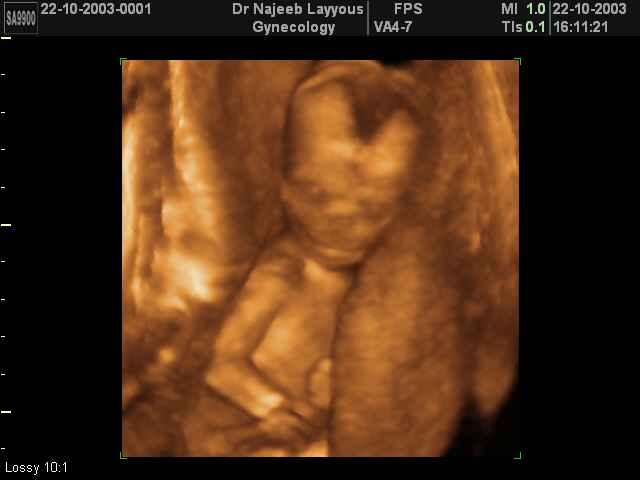

3D second trimestre échographie Photos de numérisation - deuxième partie de la grossesse | Dr N Layyous

3D second trimestre échographie Photos de numérisation - deuxième partie de la grossesse